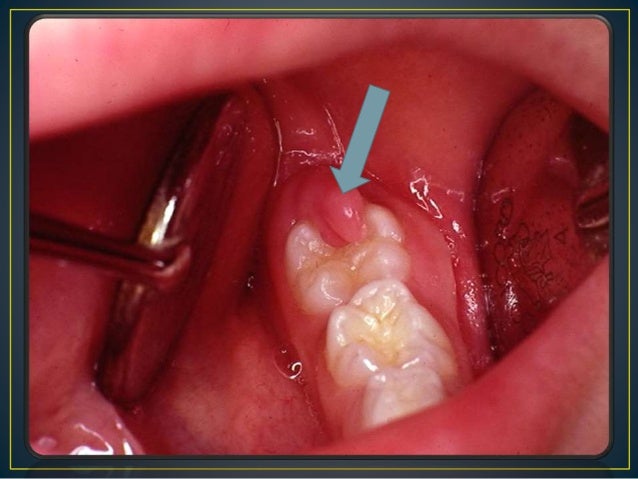

ERUPTION HEMATOMA/ ERUPTION CYST:

This is a bluish purple area found before eruption of corresponding

tooth. The colour is due to blood collected beneath the superficial layer.

Treatment is rarely needed as the tooth erupts it breaks the cyst and the hematoma disappears.